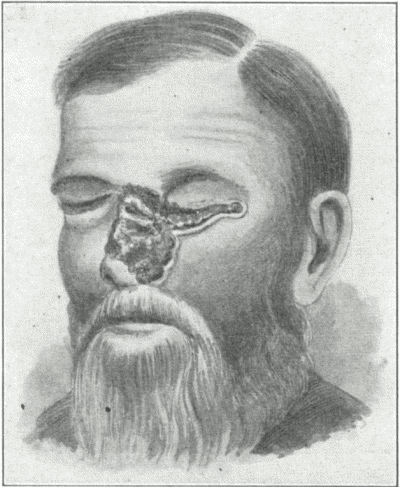

What do you understand by erythema induratum?

A rare disease characterized in the beginning by one or more usually deep-seated nodules, and, as a rule, seated in the legs, [Pg 52] especially the calf region. The nodules gradually enlarge, the skin becomes reddish, violaceous or livid in color. Absorption may take place slowly, or the indurations may break down, resulting in an indolent, rather deep-seated ulcer, closely resembling a gummatous ulcer. The disease is slow and persistent, and is commonly met with in girls and young women, usually of strumous type. It suggests a tuberculous origin.